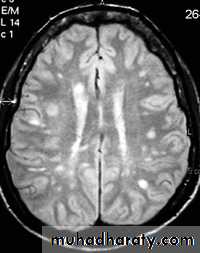

-MRI is more sensitive than CT in the demonstration of MS plaques.

- the most characteristic appearance is that of peri ventricular nodular Hyper intense lesions on T2 weighted images.

-the plaques are also well seen at the gray- white matter interfaces.

-MRI can even image lesions in the spinal cord , brainstem & cerebellum.

-multiple cerebral lesions are seen in over half the patient presenting with a single episode of optic neuritis.

-some lesion may show a central area of greater signal intensity , resembling a target.

-contrast enhancement after giving gadolinium occurs in the acute phase indicating activity & in the chronic phase doesn't enhance.

SAGITAL FLUID ATTENUATION INVERSION RECOVERY SEQUENCE: OVOID PLAQUES ( HIGH SIGNAL INTENSITY) , WHICH ARE PERPENDICULAR TO LATERAL VENTRICLE.